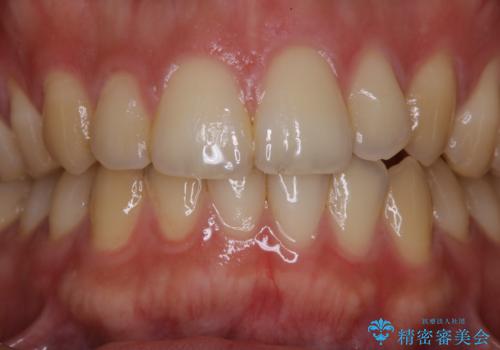

- マスクの着用により、以前より口臭が気になるとのことでした。しっかりと全体的なクリーニングを希望されたため、PMTC60分コースを行いました。

PMTCとはProfessinnal Mechanical Tooth Cleaning・専門器具による歯の機械的な清掃です。

バイオフィルム(細菌の塊)を破壊し、歯の表面をツルツルにすることでお口の中の細菌数を減らし歯周病のリスクが定着するのを防ぎます。更に、歯に新しい汚れがつきにくい状態になります。

バイオフィルムが除去されると、ご自身本来の歯の表面になります。PMTCをすることで口臭予防にもなり、定期的に行うことが大切です。